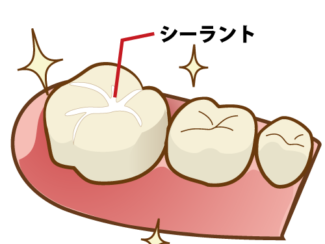

当院では、予防歯科を中心に一般歯科、小児歯科、インプラントや親知らずなどの口腔外科や

審美歯科(セラミック治療)、目立たない入れ歯や矯正歯科(マウスピース矯正)など、幅広く対応しています。